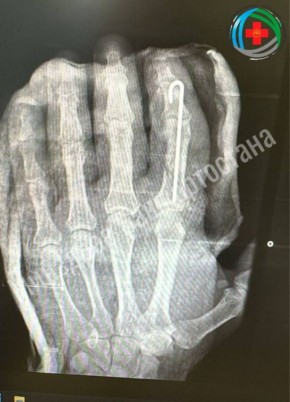

Палец успешно прижилсяЖитель Благовещенска отрубил себе палец топором во время работы во дворе.Врачи провели «ювелирную работу»: под микроскопом сшивали сосуды, кости и нервы.Сейчас пациент проходит реабилитацию. Медики...